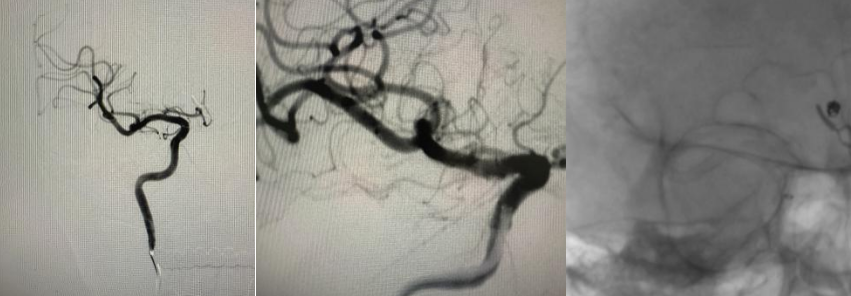

针对复发的前交通动脉瘤,小心将微导管送入瘤腔,缓慢填入栓塞材料,直至动脉瘤完全闭塞,同时确保载瘤动脉通畅,不影响正常脑组织供血;

针对新生动脉瘤,将载药支架精准送至目标位置并释放,术中多次通过血管造影确认支架贴壁良好、完全覆盖动脉瘤开口,在瘤颈处形成稳定的生物性封闭,实现血管重建。

整个手术历时约3小时,术中影像反复确认:两颗动脉瘤均完全闭塞,载瘤动脉及分支血流正常,无任何并发症迹象,手术圆满成功。